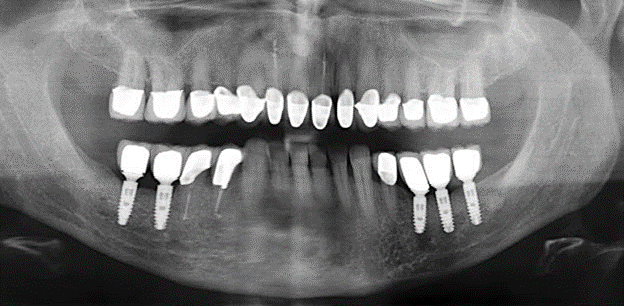

Für den klinischen Langzeiterfolg des parodontal kompromittierten Patienten ist die standardisierte und regelmäßige risikoadaptierte Betreuung im Rahmen der UPT der zentrale Baustein des Behandlungserfolgs. Dies gilt in besonderer Weise für Patienten, die nach erfolgreich abgeschlossener parodontaler Sanierung mit Implantaten versorgt wurden (Abb. 11a und b).